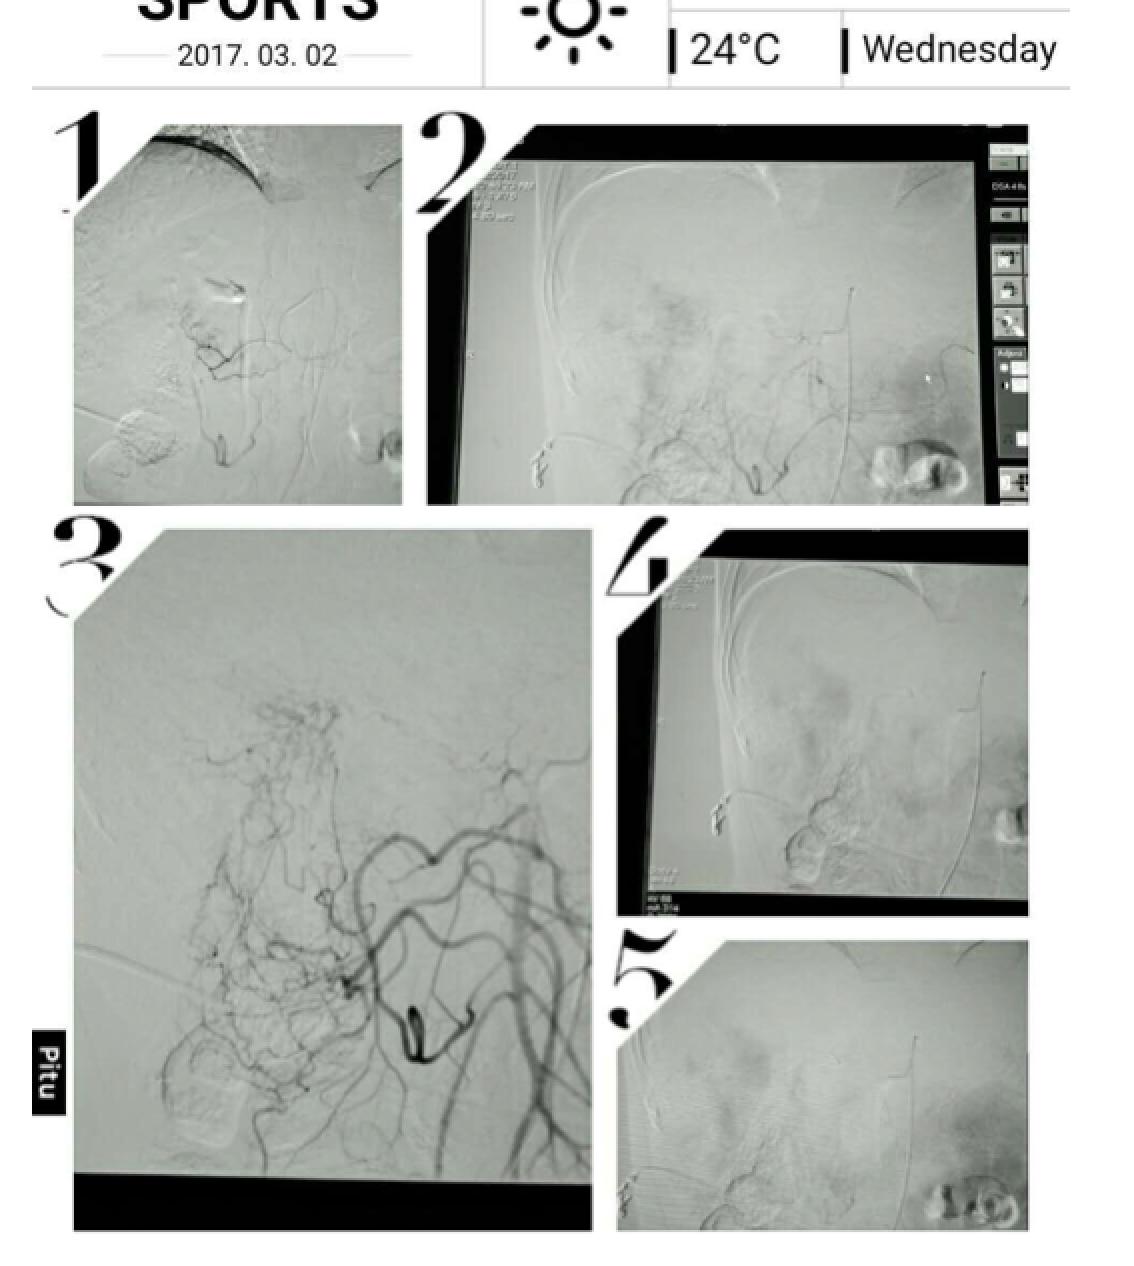

患者因纳差、烧心、腹痛、腹胀2月,于2016-01-17在某县人民医院行腹部CT示肝癌并门脉癌栓形成。分别于2016-01-22、2016-02-19于某市医院行两次TACE术(具体不详)。患者介入术后规律服用抗乙肝病毒、保肝、提高免疫力等药物治疗。2016-02-03至2016-04-30在某省立医院行5周期CIK免疫治疗。2016-05-18至2016-05-25于我院行射波刀治疗门静脉癌栓,具体放疗计划为:42Gy/7F。2016-06-24在我院行肝右动脉化疗栓塞术+肝右动脉灌注化疗术+间接门脉灌注化疗术,术中化疗总量,吡柔比星2mg、顺铂12mg、氟尿嘧啶250mg。分别于2016-05-10、2016-05-27、2016-06-13、2016-07-01、2016-07-27、2016-08-22、2016-09-19、2016-10-07、2016-10-19、2016-11-18、2016-12-18、2017-02-18行12周期免疫治疗。自2016-05-12起患者间断口服靶向药物阿帕替尼250-500mg/d,血压维持在220-130/95-70mmHg,血压升高期间伴上腹部不适,左侧为著,并向腰背部放射,偶尔反酸、烧心,剑突下疼痛,口服抑酸剂或进食后缓解,临床诊断为十二指肠溃疡,目前口服奥美拉唑、马来酸依那普利、氢氯噻嗪等药物对症降压。2017-03-02于我院行第二次肝右动脉化疗栓塞术+肝右动脉灌注化疗术+间接门脉造影术+肠系膜上动脉灌注化疗术。术中化疗总量,洛铂10mg、氟尿嘧啶500mg、吉西他滨400mg。目前间或皮下注射胸腺法新、重组人干扰素α-2b提高免疫力及慢性乙型病毒性肝炎治疗效果。

患者相关影像资料